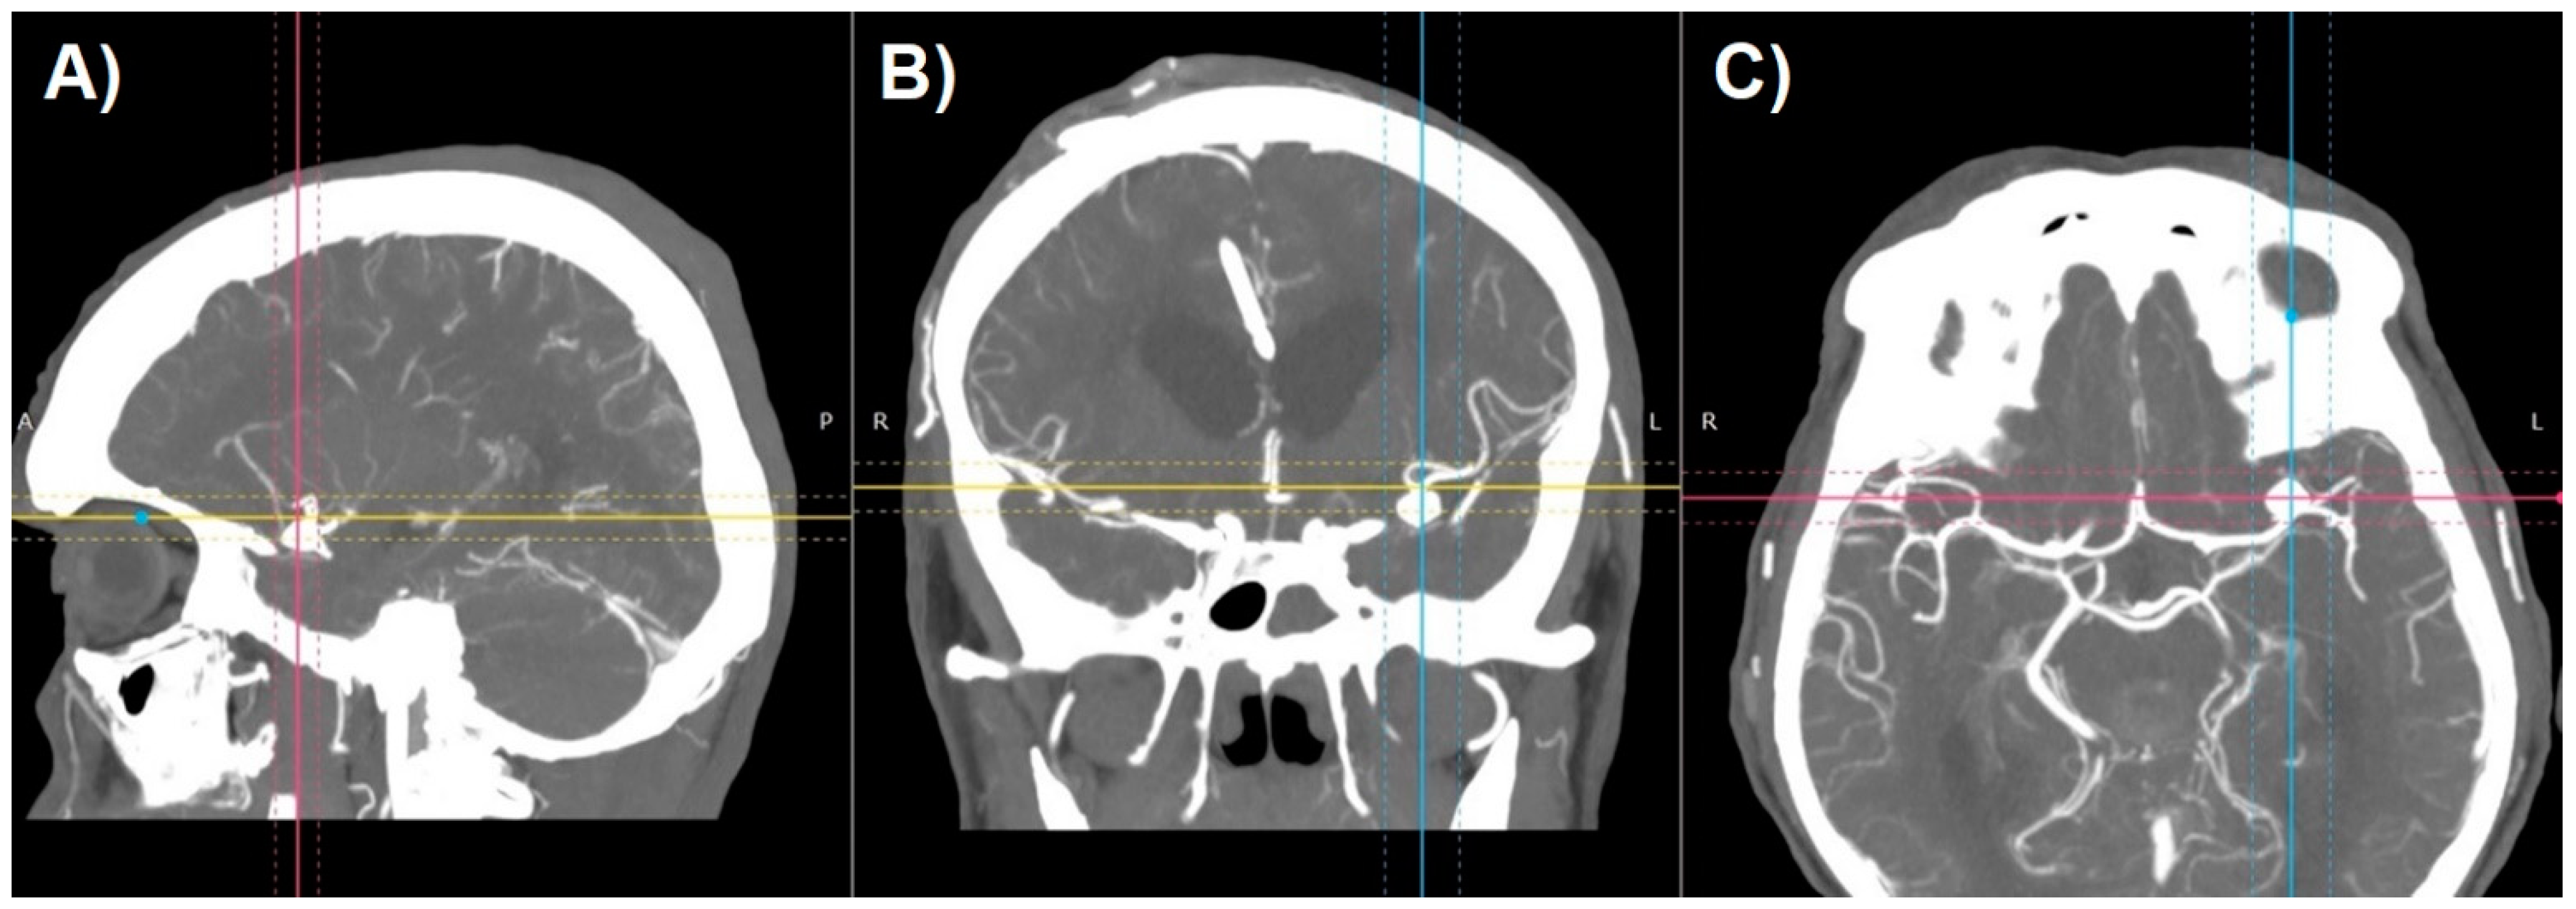

Aneurysm management starts with a thorough analysis of the anatomy. Raw image data from CT-angiography create axial slices through the examined part of the anatomy and can be converted to create sagittal and coronal projections (Figure 1). Unfortunately, because of the two-dimensional nature of such images, they usually fail to provide an accurate perception of treated pathology. Most DICOM viewers allow to perform the reconstructions of such images to create more like-3D images. Maximum Intensity Projection (MIP) and shaded surface display volume rendering techniques (SS-VRT) are mostly utilized. As it is shown in Figure 2, the first one consists of projecting several slices with the highest attenuation value on every view throughout the volume onto a 2D image [8]. Considering vascular diseases, this technique allows to trace the course of vessels neighboring to the aneurysm, thus producing the opportunity to visualize the pathology in a way accurate enough for preoperative planning.

Figure 2.

Maximum Intensity Projection reconstruction of CT-angiography of patient with cerebral aneurysm in (A) sagittal, (B) coronal, and (C) axial plane.